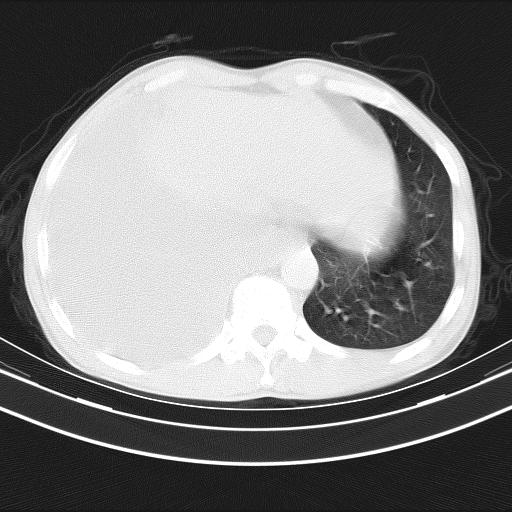

男性,44岁,结核病史多年。现胸闷气短,咳嗽,偶咳血。

1)两肺继发性肺结核伴空洞形成,左肺多发性结核球。2)右侧大量胸腔积液伴右肺部分膨胀不全。3)纵隔淋巴结肿大。

1,双肺多发结节 并空洞影改变, 左侧胸腔积液并部分包裹, 结合原病史首先考虑结核. 但也不除外其它.

吉大一院胸水抽检结果:结核性胸水